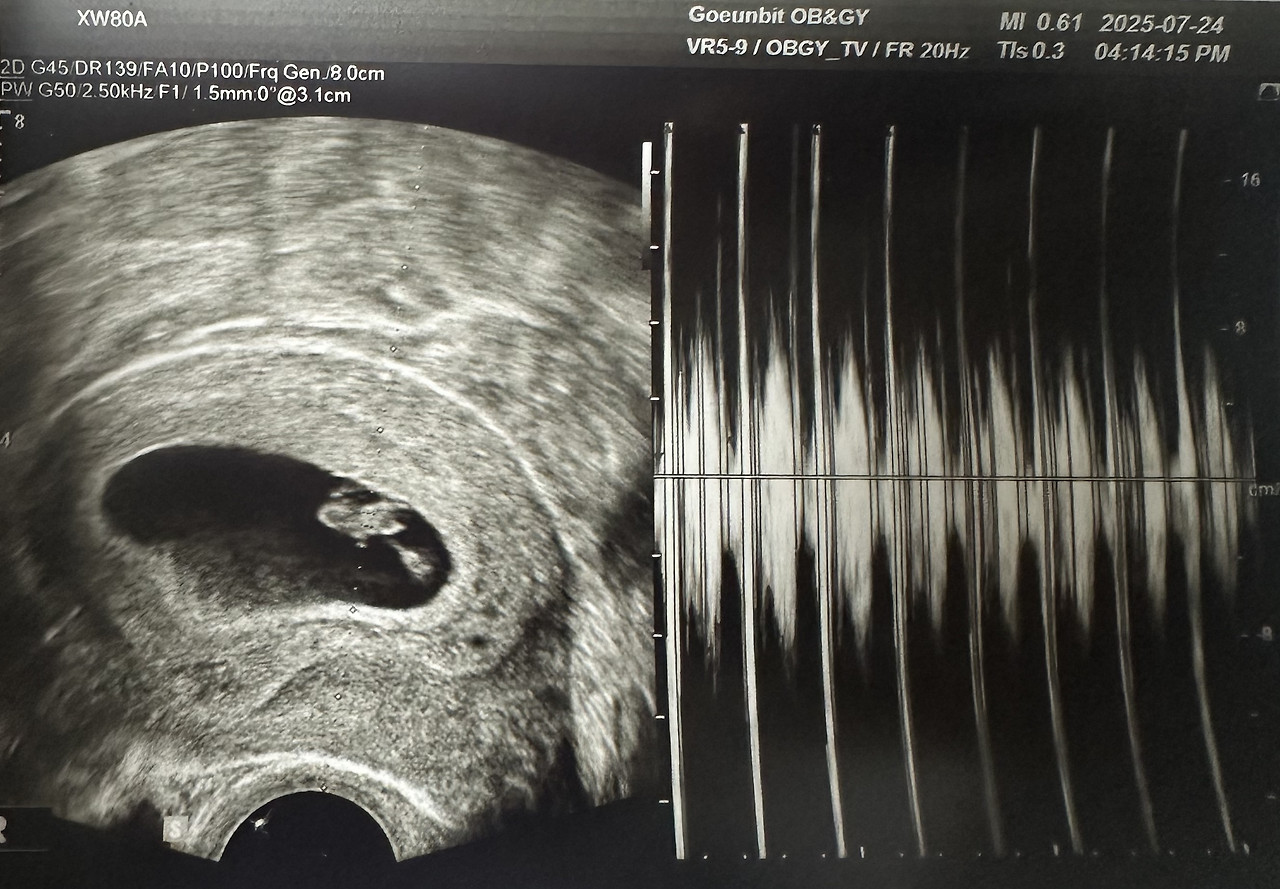

7주 차, 심장 소리를 듣다

드디어 아기의 심장 소리를 들었다.

7주 차 아기의 모습. 작지만 또렷하게 심장이 뛰고 있었다.